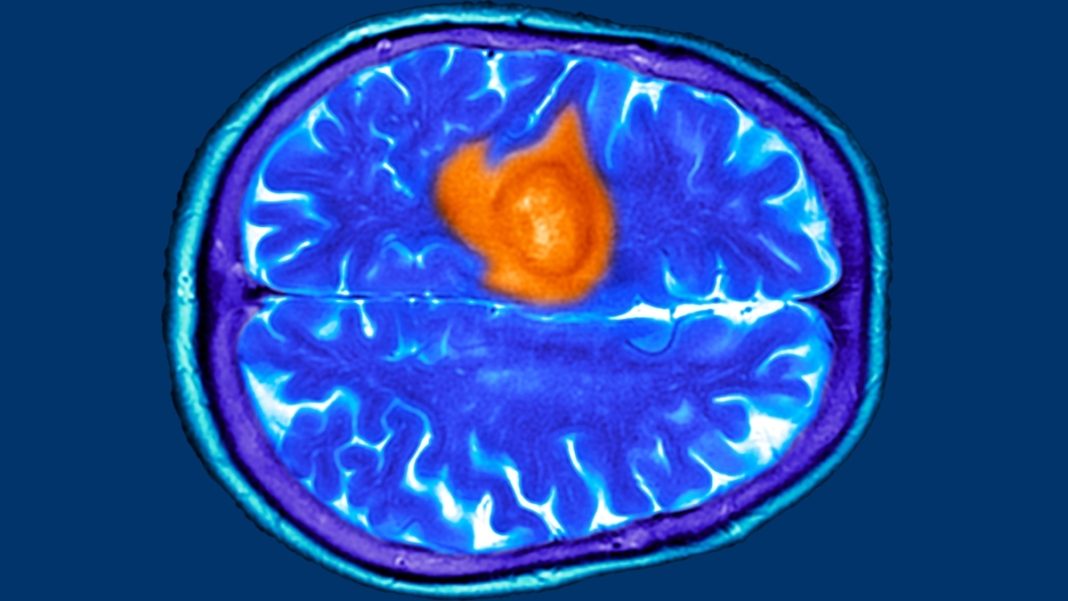

Σύμφωνα με την Laura Standen, διδακτορική ερευνήτρια στο Ινστιτούτο Wolfson σε άρθρο που δημοσιεύει αναφέρεται στα 7 προειδοποιητικά σημάδια του καρκίνου του εγκεφάλου. Όπως σημειώνει η ίδια ως μέρος της έρευνάς της, την οποία μπορείτε να βρείτε εδώ, με όσους ασθενείς έχει μιλήσει κατά τη διάρκεια της ακαδημαϊκής της καριέρας, όλοι της ανέφεραν ένα κοινό στοιχείο.

Το γεγονός δηλαδή ότι όλοι είχαν συμπτώματα πολύ πριν τη διάγνωση, τα οποία αγνοούσαν και δεν έδωσαν την απαραίτητη προσοχή. Απλά καθημερινά γεγονότα, όπως δηλαδή μια απλή ζάλη, δυσκολία στο να βρούμε την κατάλληλη λέξη, ή απλά γεγονότα όπως να έχουμε ξεχάσει πού έχουμε τοποθετήσει το κινητό μας, Όλα αυτά μπορεί να είναι πρώιμα σημάδια καρκίνου του εγκεφάλου, σύμφωνα με την ίδια.

Βέβαια, εδώ θα πρέπει να γίνει μια σημαντική επισήμανση. Το γεγονός ότι κάποιος εμφανίζει κάποιο από τα συμπτώματα που ακολουθούν παρακάτω, δε σημαίνει απαραίτητα ότι έχει καρκίνο του εγκεφάλου και το άρθρο σε καμιά περίπτωση δεν έχει σαν σκοπό να αντικαταστήσει την ιατρική συμβουλή και διάγνωση.